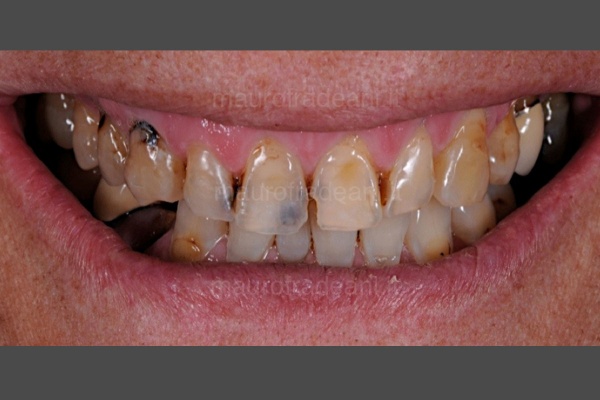

I principali trattamenti quali otturazioni e ricostruzioni, volti a preservare il più possibile la sostanza dentale ripristinando l’integrità dei denti, si effettuano con materiali ad alta valenza estetica: resine composite o ceramica che garantiscono un risultato eccellente e stabile nel tempo.

Solo dopo un’attenta valutazione della natura e tipologia delle discromie l’odontoiatra o l’igienista potranno suggerire il trattamento più indicato e risolutivo.